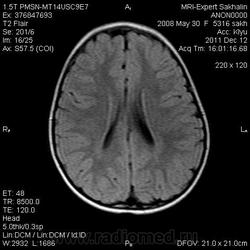

Девочка 3 года.В анамнезе -родовая травма-внутрижелудочковые кровоизлияния 1-2 ст.Задержка психического развития.Со слов мамы, "бывают истерики, хватается ручками за голову, особенно затылочную часть".Как интерпретировать изменения в желудочках, в задних рогах?Ликворную кисту ЗЧЯ отметила.

Киста не совсем киста, но нижняя ретроцеребеллярная цистерна незначительно расширена- я указала.

Коллеги, в рамках ликбеза: а такое (некоторое) расширение субарахноидального пространства (не вполне характерное для 3-летнго ребенка), расценивается как гидроцефалия (заместительная, открытая, последствие ишемически-гипоксического синдрома) или нет?

В данном исследовании я не отмечала наружную гидроцефалию.